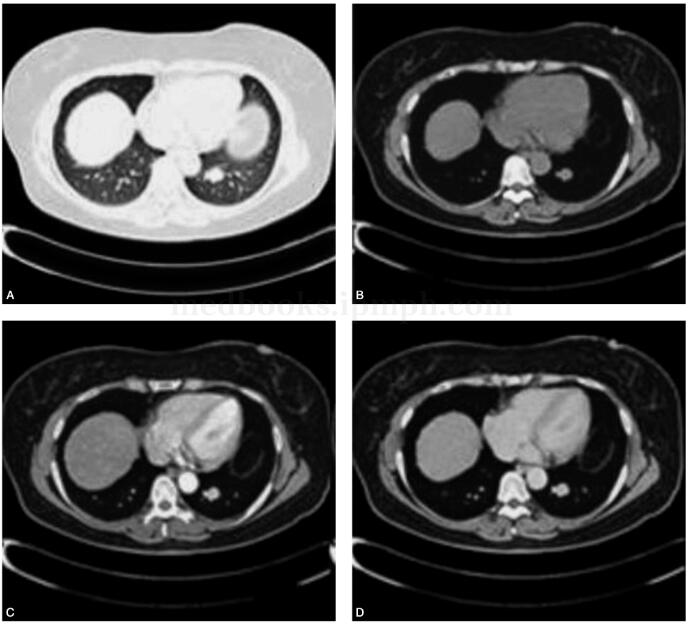

女,51岁,咳嗽伴胸闷、胸痛5个月余。患者5个月前无明显诱因出现间断性咳嗽,夜间咳嗽较重,无咳嗽、咯血,尚能忍受,间断性自服抗生素(罗红霉素、阿莫西林)后无明显缓解,伴胸闷、咯血,发病期间偶有头晕、心慌,无气短,无盗汗、乏力,无发热、寒战。半月前于外院就诊,行CT平扫检查显示:左肺下叶占位性病变,考虑良性病变。为确诊前来我院就诊。行增强CT检查,左肺下叶结节占位,界清,可见强化,可符合硬化性血管瘤。2010年10月29日手术,术后诊断显示瘤细胞大部分排列成大小不等血管样,少部分区域呈乳头状,实性片状排列,部分细胞圆形,部分细胞立方状(图1)。

图1肺窗显示左肺下叶后底段类圆形高密度结节,界清。纵隔窗显示左肺下叶后底段结节边缘呈软组织密度影,中心密度略低。增强扫描左肺下叶后底段结节周边实性部分强化明显,中心低密度区未见明显强化